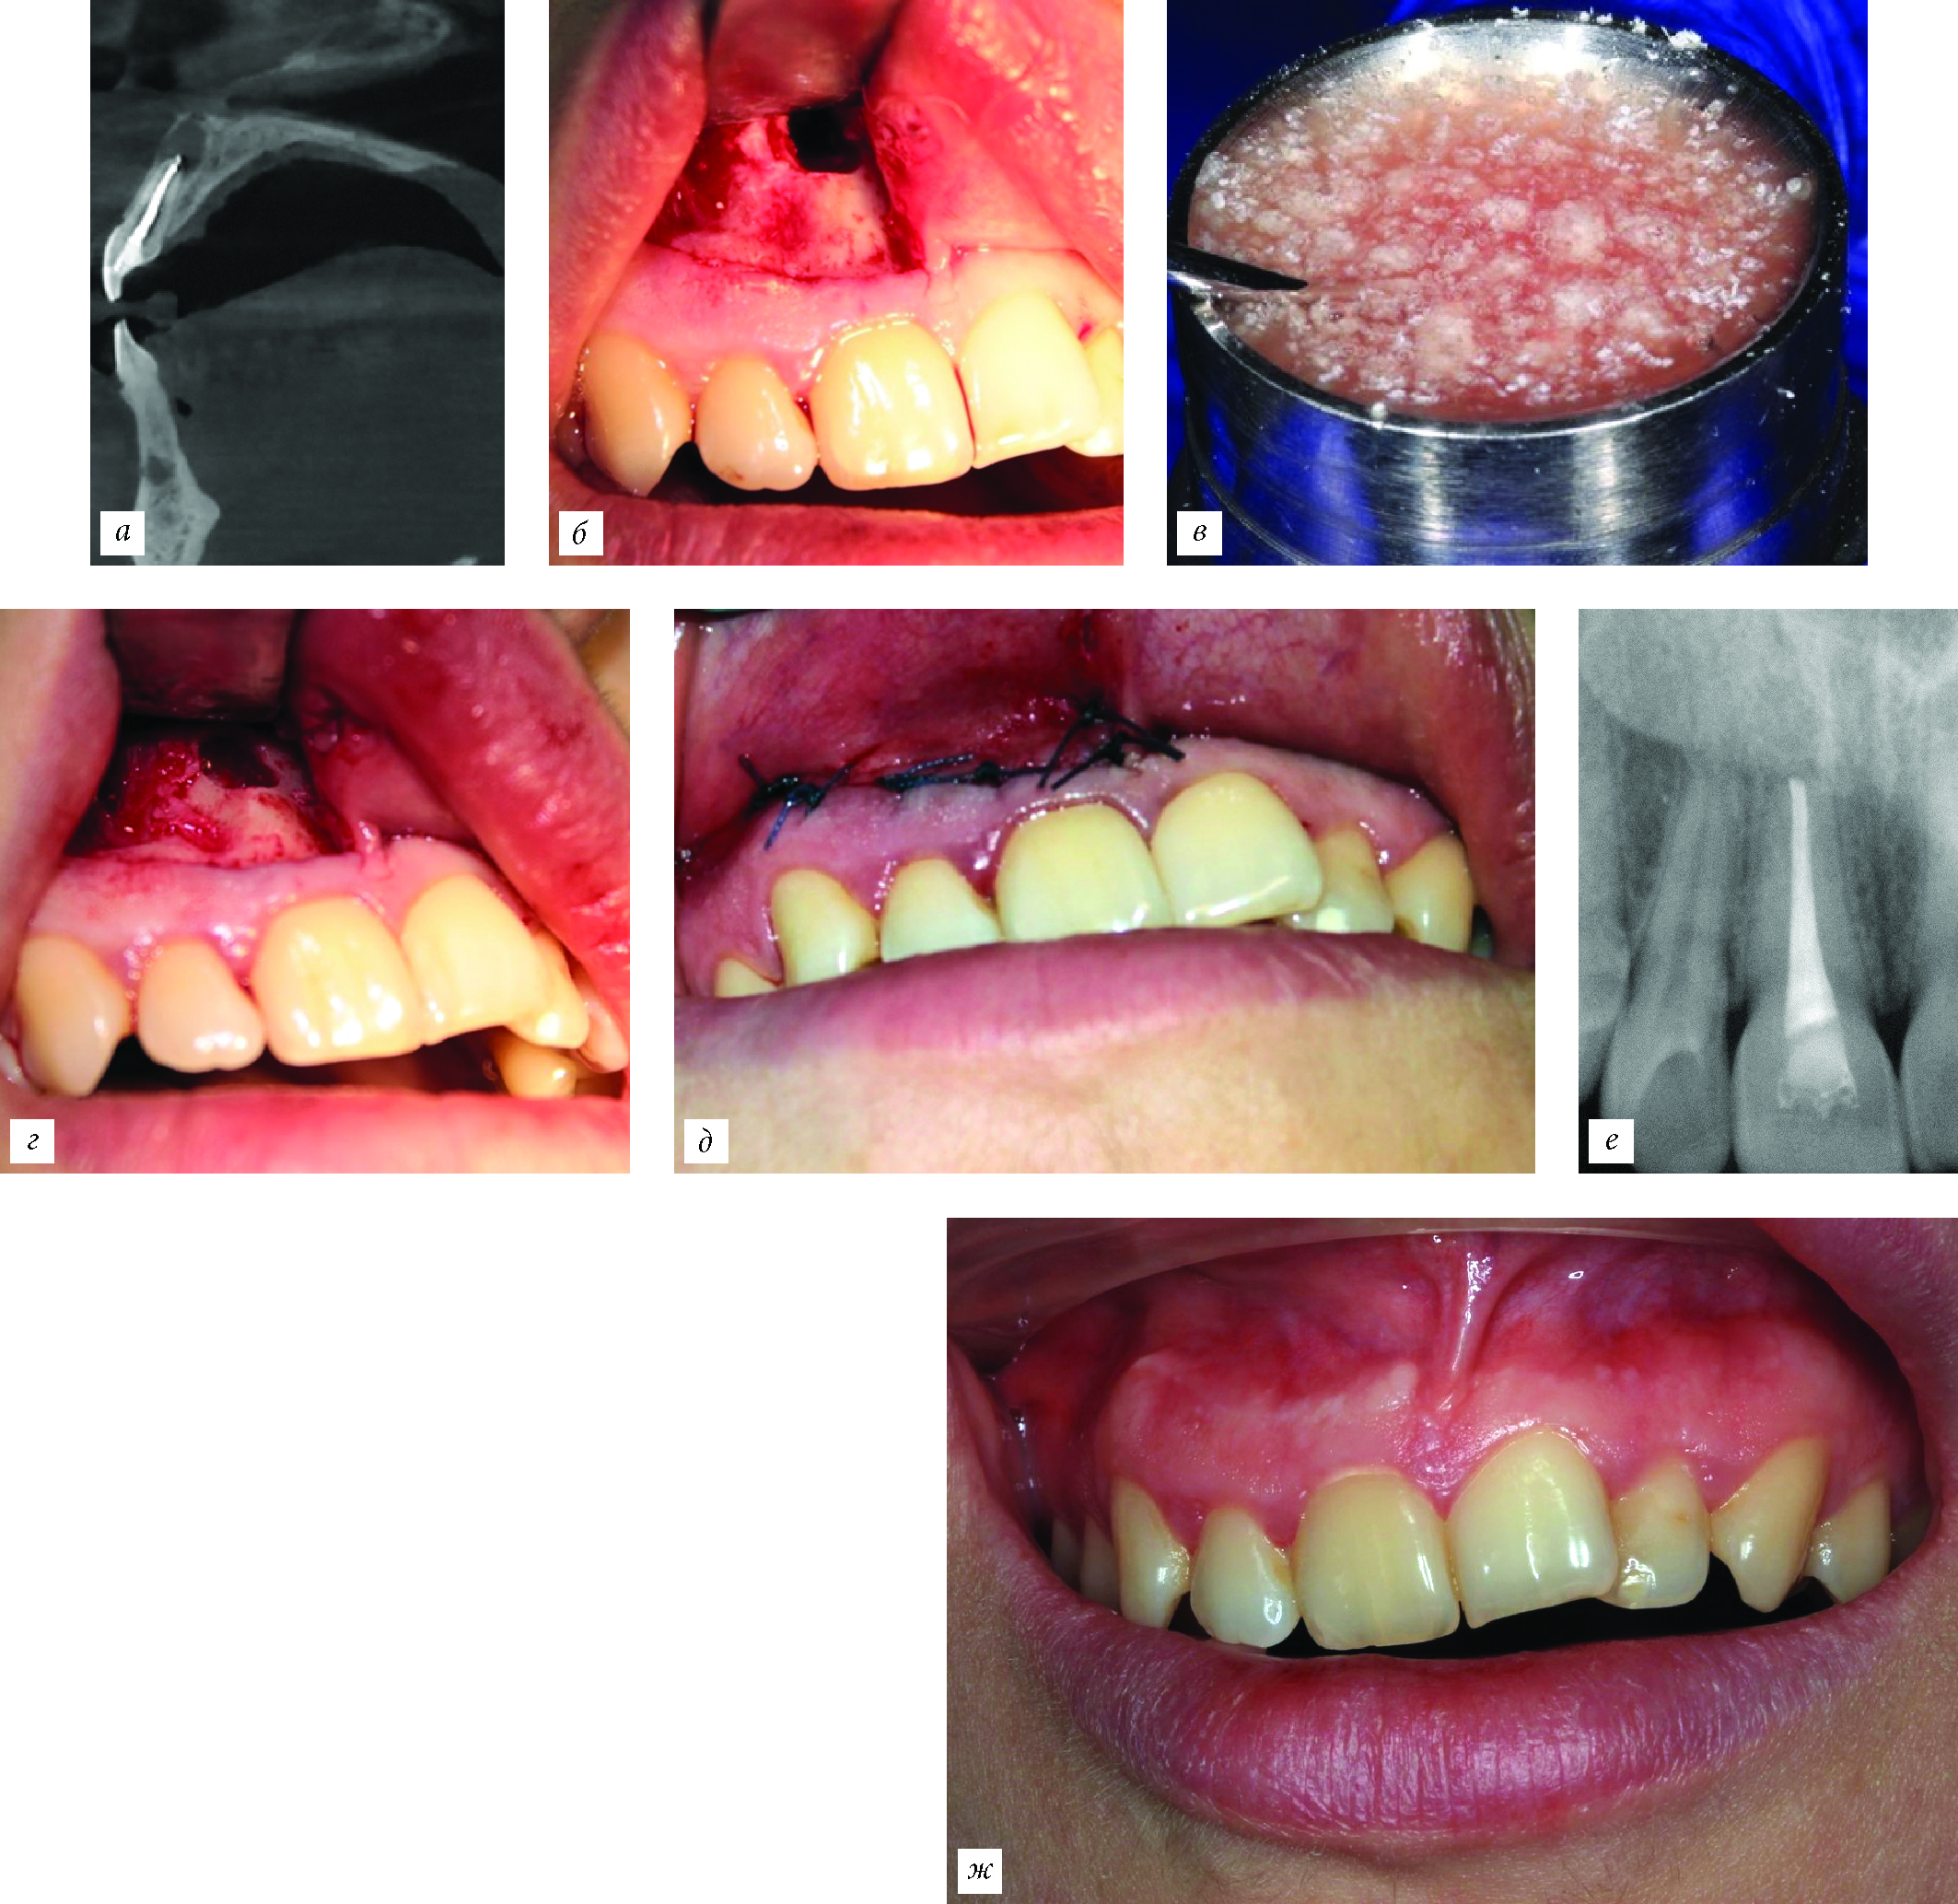

Материал на основе ксеноколлагена 1-го типа не рентгенконтрастен, что позволяет более точно оценить эффект от его применения в послеоперационном периоде (по сравнению с ксено- или аллогенной костной тканью), когда в ходе этапов репаративного остеогенеза он полностью замещается костной тканью (рис. 9).

Рис. 9. Применение коллагенового материала, смешанного с физиологическим раствором, при операции резекции верхушки корня. а — срез компьютерной томограммы — очаг разрежения костной ткани в области верхушки зуба 2.1; этапы операции: б — костный дефекта; в — материал смешан с физиологическим раствором; г — дефект заполнен материалом; д — наложение швов; е — контрольная рентгенограмма через 6 месяцев после операции; ж — полость рта через 6 месяцев после операции.